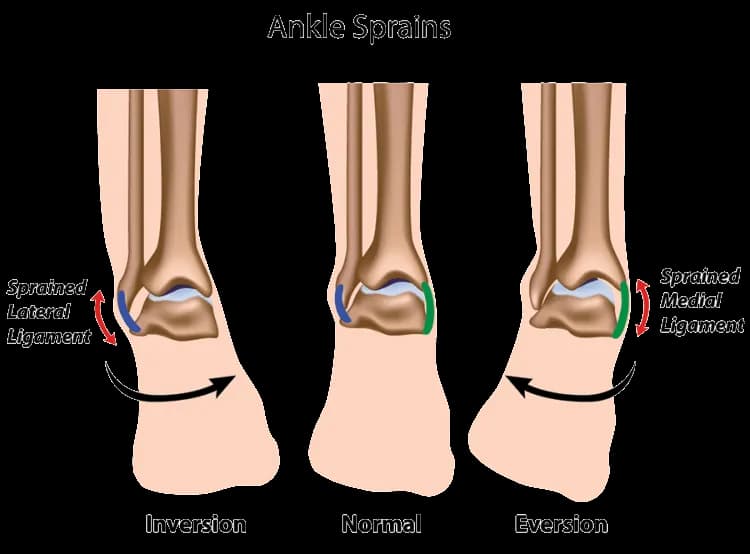

Skręcenie stawu skokowego - ile trwa leczenie i co warto wiedzieć

Skręcenie stawu skokowego ile trwa leczenie? Dowiedz się, jakie są czasy regeneracji i jak skutecznie wspierać proces powrotu do zdrowia.

Skręcenie stawu skokowego - ile trwa leczenie i co warto wiedzieć

Skręcenie stawu skokowego ile trwa leczenie? Dowiedz się, jakie są czasy regeneracji i jak skutecznie wspierać proces powrotu do zdrowia.